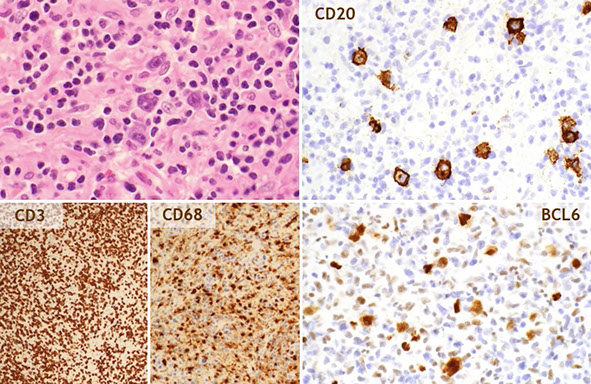

T-cell/histiocyte-rich large B-cell lymphoma (TCHRLBCL)